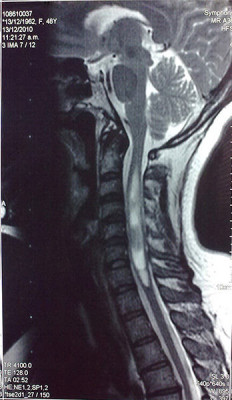

Casos Neuroloquirúrgicos

Envíado por Dr. Ruben Eduardo Amaya Contreras